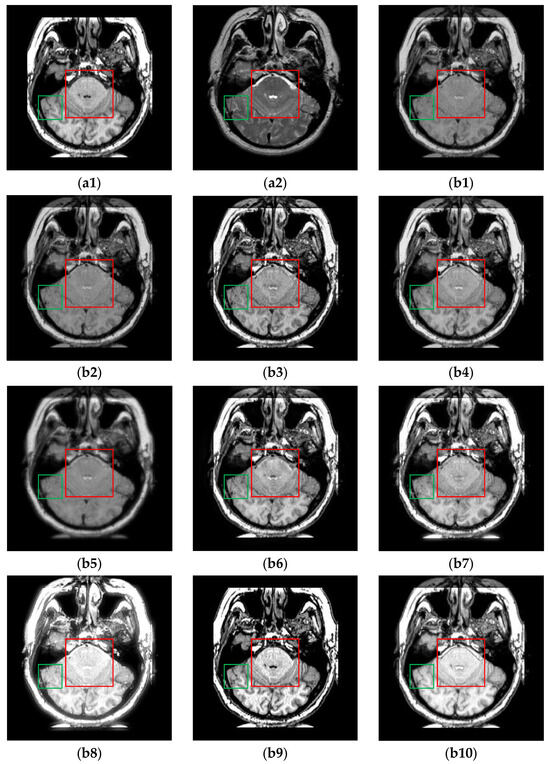

The fusion results of the CT-MR image pairs are shown in Figure 6. Clearly, ReLP, TIF and CIRF outperform other methods in preserving the white cranium cross-section from the CT image. From the green boxes and the yellow arrows, we can clearly observe that only U2Fusion, DenseFuse and CIRF can simultaneously preserve low-intensity information and retain crucial information from the CT image. However, CIRF produces the fused result with higher contrast than U2Fusion and DenseFuse. The fused results marked with the red boxes show that CIRF can preserve the details from MR images better than other methods. Therefore, it is evident that CIRF simultaneously retains the features derived from both CT and MR images, which indicates its strong feature extraction and fusion capability.

Figure 6. The results of all algorithms on the CT-MR image pairs from Atlas dataset. (a1) Source CT image; (a2) Source MR image; (b1) U2Fusion; (b2) DenseFuse; (b3) IFCNN; (b4) NestFuse; (b5) RFN-Nest; (b6) PAPCNN; (b7) ReLP; (b8) TIF; (b9) CDDFuse; (b10) CIRF.